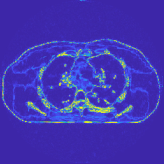

This paper was inspired by a simple observation related to our recent study [34]: for the penalized weighted-least squares (PWLS) reconstruction method using prior with a learned ST (PWLS-ST-) [34], the sparsification error histograms match a Laplace distribution over the iterations; see Fig. 1. The question then arises, “Does the learned prior experience model mismatch in testing stage?” To answer this question, we aim to investigate learned STs for regularization. This paper

The term denotes a -based sparsification error [3, 4, 5]. We expect to be more robust to sparsity model mismatch than the -based sparsification error used in [34, 36]. Fig. 1 shows histograms of sparsification error at different outer iterations of the PWLS-ST- method. Over the iterations, the sparsification error histograms appear more like a Laplace distribution than a Gaussian distribution. This observation suggests that the proposed prior model is more suitable than the prior model for PWLS-ST-based reconstruction. Section III-B1 shows that the proposed -based sparsification error term, , improves the accuracy of reconstruction compared to the prior model in [34, 36].